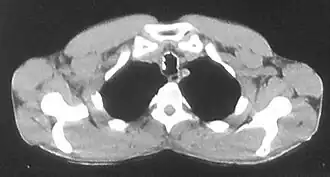

![]() Изображение трахеи с включениями хрящевой и костной плотности по ходу её стенок при остеохондропластической трахеобронхопатии | |

При компьютерной томографии выявляются цепочки выступающих в просвет дисковидных включений хрящевой и костной плотности по ходу стенок трахеи и бронхов с деформацией и сужением просвета всей дыхательной трубки или отдельных её сегментов в хрящевой части[2][8][17][23][25][26].